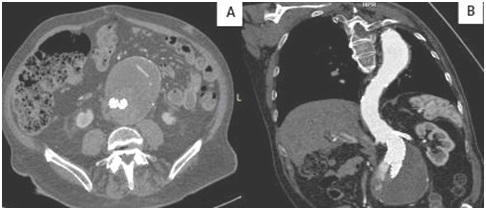

El paciente se coloca en decúbito supino y se realiza en primer lugar, un barrido desde la apófisis xifoides hasta la bifurcación aórtica y ambas ilíacas con la sonda curva en modo B. Así se visualiza la posición de la endoprótesis, se valoran posible migración y se mide el diámetro máximo en el plano axial, tanto el AP como el transverso (Fig. 4). Posteriormente, se inicia la imagen doppler color de forma sistémica para objetivar endofuga de alguna rama visceral o lumbar dentro del saco aneurismático.

Fig. 4. Control del diámetro máximo de AAA tras reparación con endoprótesis

fenestrada y embolización previa con “coils” de arteria mesentérica inferior.

En el caso de realización de TC en aquellos casos con insuficiencia renal crónica, el paciente ingresa para nefroprotección renal mediante fluidoterapia las doce horas previas y posteriores a dicha prueba diagnóstica (Fig. 5). Luego, se da el alta hospitalaria con seguimiento por nuestro servicio y control analítico a la semana con su nefrólogo de referencia.

Fig. 5. Imagen A: Endofuga tipo II (arteria mesentérica inferior). Imagen B: Endofuga tipo IA.